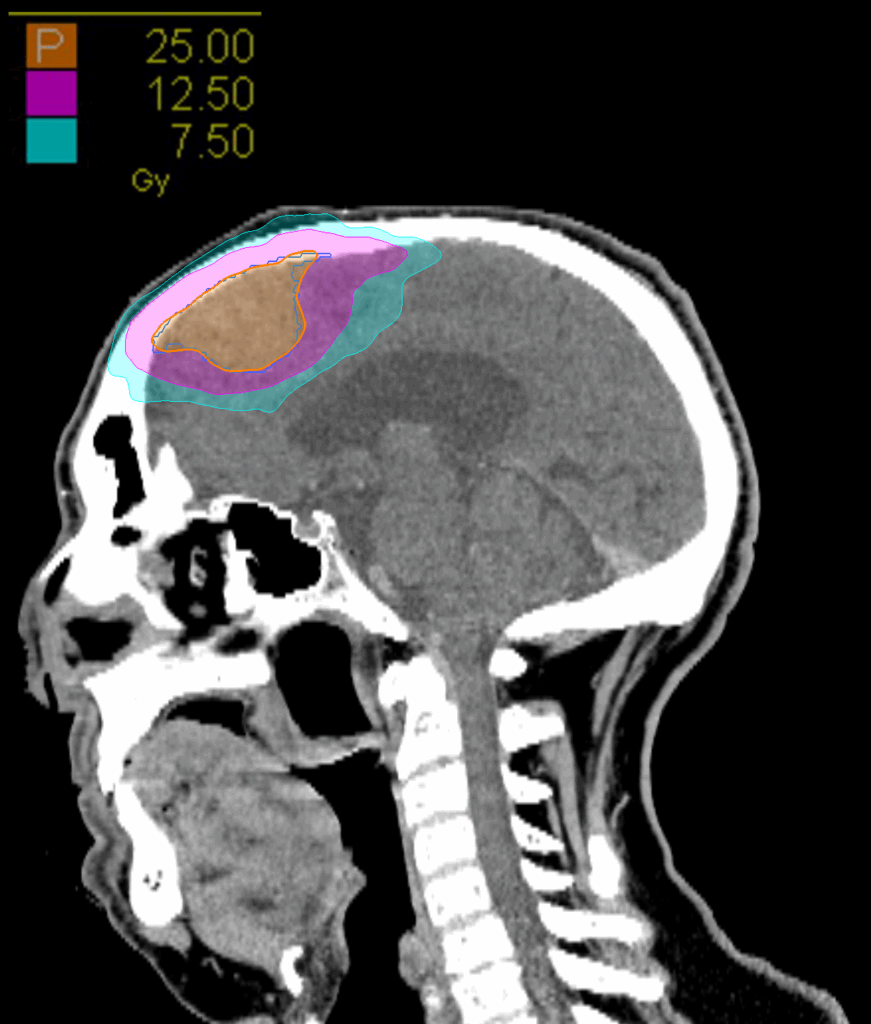

Treatment Plan Images

Fractionation

25 Gy in 5 fractions

PTV(s) Volume

PTV, 27.6 cc

Dose Distributions

- Prescription to the 83.2% isodose line

- Max. dose 30.1 Gy

New Conformality Index (nCI)

nCi = 1.24

Gradient Index (GI)

GI = 3.88